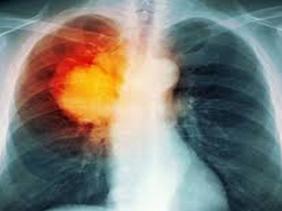

كشف الأطباء و الأخصائيون المشاركون في الطبعة التاسعة للأيام الدراسية المخصصة هذه السنة للحديث عن سرطان الرئة أن هذا المرض في تزايد مستمر بالجزائر، وذلك بإحصاء أكثر من 3500 حالة جديدة سنويا و أن 80 بالمائة حالات ميئوس منها لاكتشاف المرض في حالاته المتقدمة.

و أشار في هذا الصدد البروفيسور كتفي من مصلحة الرئة من المؤسسة الاستشفائية للرويبة بالجزائر العاصمة أن التشخيص المتأخر للداء وراء ارتفاع الحالات المسجلة، مشيرا إلى أنه و بالرغم من الاستثمار المادي الهام الذي يتطلبه علاج هذا الأخير إلا أن نسبة حظوظ شفاء المريض المصاب تبقى جد ضئيلة.

و يأتي هذا اللقاء الذي استعرض فيه الأطباء مختلف تقنيات العلاج الخاصة بعلاج سرطان الرئة حيث ركزوا على التقنيات الجديدة للكشف عن الأورام السرطانية و منها استعمال الرنين المغناطيسي حسب رئيس الجمعية مصطفى موساوي في إطار التحسيس بهذا الداء و الحد من الانتشار الواسع له.